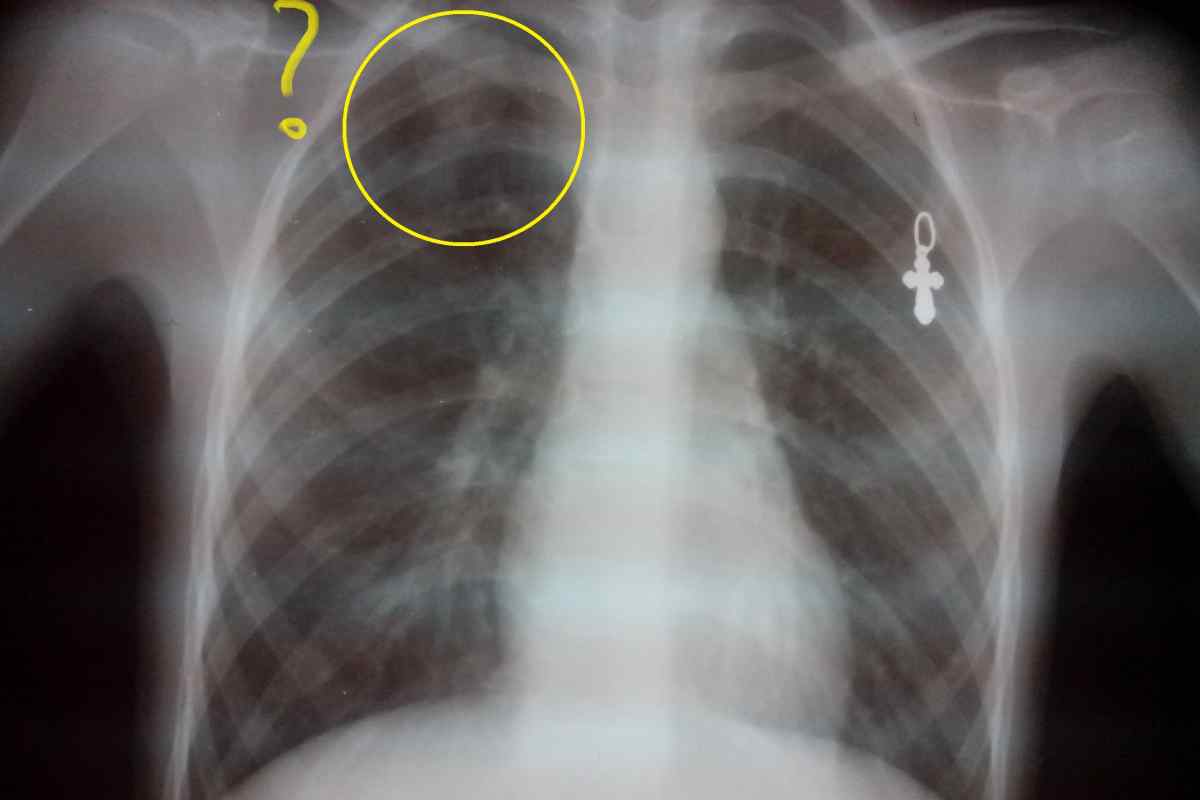

Нормальная рентгенограмма легких: что нужно знать

Раздел: Мудрость в объективе